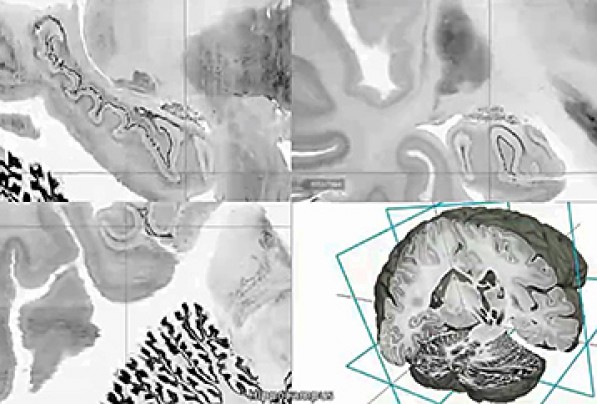

The digital three-dimensional model called "BigBrain" was produced from the thousands of sections made from the brain of a 65-year-old woman. Its resolution is finer than a human hair, so it can reveal clusters of brain. A 65-year-old woman’s brain was cut into 7,400 slices to create the most detailed three-dimensional atlas of the human brain ever made, bringing researchers one step closer to reverse-engineering the brain’s convoluted circuitry. Brain atlases are essential reference tools for researchers and physicians, to determine which areas are “lighting up” during a task or thought process, or during image-guided surgery. The better the atlas resolution, the better doctors can target ever-smaller parts of the brain and their individual function. The atlas creators, who are from Canada and Germany, have made the ultrahigh-resolution model — 50 times more detailed than a typical scan — publicly available in a free online format. The authors also published their work in the journal Science on Thursday. The atlas, called BigBrain, offers a common basis for open, worldwide scientific discussion on the brain, said author Karl Zilles of the Heinrich Heine University Düsseldorf. Zilles pointed to a novel treatment for Parkinson’s disease called deep brain stimulation, where electrical impulses are sent through electrodes implanted into specific points in the brain. He said BigBrain may open the doors for more accurate localization of electrode placement and thus render treatment more effective. After staining and digitizing the thousands of plastic-wrap-like slices, the nearly cellular resolution map revealed the network of layers, fibers and microcircuits of the woman’s brain. While variation exists among brains, across ages and individuals, they have largely the same distribution of brain structures and anatomy, said author Alan Evans of McGill University’s Montreal Neurological Institute. There are “subtle shape changes among individuals,” but all atlases start from one representative brain and go from there. The team was chiefly limited by computing power and capacity. To map the human brain with 1 micron spatial resolution, which has been done for mouse brains, the atlas would take up 21,000 terabytes of data — essentially rendering it impossible to navigate. By comparison, BigBrain, with its 20 micron resolution, comprises about a terabyte of data. Prior MRI-based atlases had resolution of 1 millimeter. Richard Leigh, a Johns Hopkins neurologist, said he’s looking forward to test-driving BigBrain for his research on stroke recovery. With the microscopic detail available, Leigh can see which particular groups of neurons are growing through stroke treatment rather than just a general fuzzy area. Evans was in Seattle on Wednesday working with the Allen Institute for Brain Science. Created by Microsoft co-founder Paul Allen, who has committed $500 million since its start in 2003, the Allen Institute has assembled a less-detailed human brain atlas of its own. BigBrain is part of the European Union’s Human Brain Project that brings together specialists in neuroscience, medicine and computing to decipher the mysteries of the brain. President Obama announced in April an initiative to map the human brain, describing it as a way to discover cures for neurological disease and strengthen the economy. |